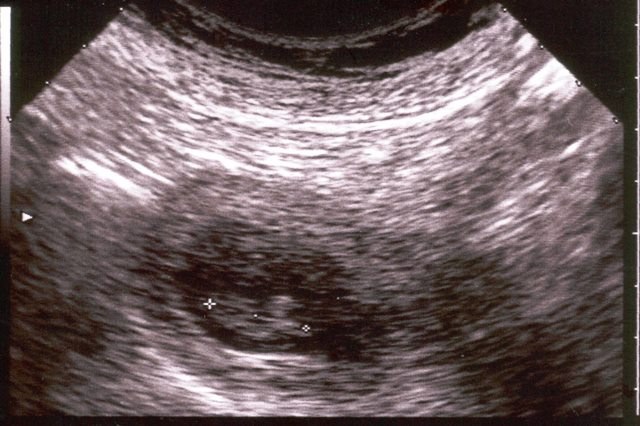

È nata qui, quarant'anni fa. Ma l’ecografia, grazie alla tecnologia, sta conoscendo una seconda giovinezza. E al Sant’Orsola si stanno sperimentando diverse possibili evoluzioni per l’utilizzo degli ultrasuoni nella diagnostica e nella cura. Un futuro di possibilità su cui si farà il punto oggi nel corso del convegno “40 anni dopo, l’ecografia del domani”, nell’Aula Murri del Policlinico di Sant’Orsola, organizzato da Luigi Bolondi, direttore dell’Unità operativa di Medicina interna, presidente della Scuola di Medicina e chirurgia dell'Università di Bologna e protagonista della storia dell’ecografia a Bologna.

“Il nostro Policlinico - spiega il professor Bolondi - è stato uno dei primi ospedali in Europa a sperimentarne l’uso degli ultrasuoni nella diagnostica clinica. Tutto iniziò quasi per caso quando insieme alle attrezzature richieste per i laboratori una multinazionale giapponese ci inviò il prototipo di un nuovo strumento da testare”. Era il primo ecografo e toccò proprio a Bolondi, allora studente di Medicina, provarlo e studiarlo, fino a redigere la propria tesi di laurea e a portare i primi risultati in congressi nazionali nel 1974.

Il lavoro avviato allora non si è mai fermato. Negli anni ’80 e ’90, così, con l’introduzione della tecnologia della “scala dei grigi” e quindi del Doppler, nonché delle tecniche interventistiche ecoguidate, si è notevolmente ampliata la gamma delle prestazioni. Questa attività ha portato alla creazione del Centro universitario di Ecografia internistica presso il quale si sono formati centinaia di medici provenienti da tutte le parti d’Italia e del mondo. A Bologna è stata fondata la Società Italiana di Ultrasonologia in Medicina e Biologia ed è stato attivato il dottorato di ricerca in Ultrasonologia.